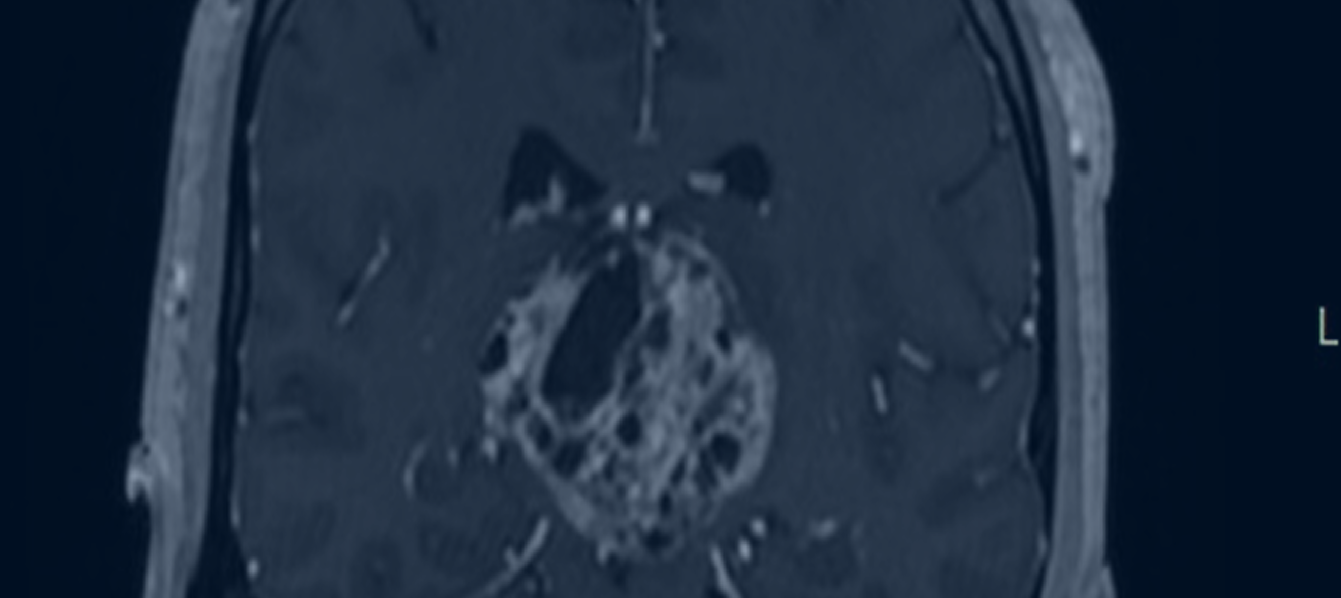

• Μαγνητική Τομογραφία Εγκεφάλου, για την ανάδειξη της φύσης και της έκτασης του όγκου.

Υπάρχουν διάφορες τεχνικές για τη χειρουργική εξαίρεση των όγκων επίφυσης, με πιο συνηθισμένη την υποινιακή κρανιοτομή. Η εκτομή τους θέτει ορισμένες προκλήσεις, όπως βαθύ χειρουργικό πεδίο, ζωτικής σημασίας παρακείμενες νευραγγειακές δομές και στενός διάδρομος εργασίας. Ωστόσο, στα χέρια ενός έμπειρου κι εξειδικευμένου νευροχειρουργού η εκτομή των όγκων επίφυσης διενεργείται με απόλυτη ασφάλεια κι αποτελεσματικότητα, αποφεύγοντας τον τραυματισμό του στελέχους ή των αγγείων του εν τω βάθει φλεβικού συστήματος.